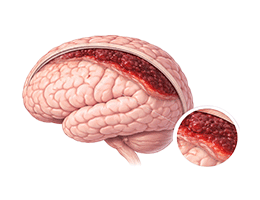

뇌출혈 (ntracerebral Hemorrhage)

경막하혈종 (Chronic subdural hematoma)

지주막하출혈 (Subarachnoid hemorrhage)